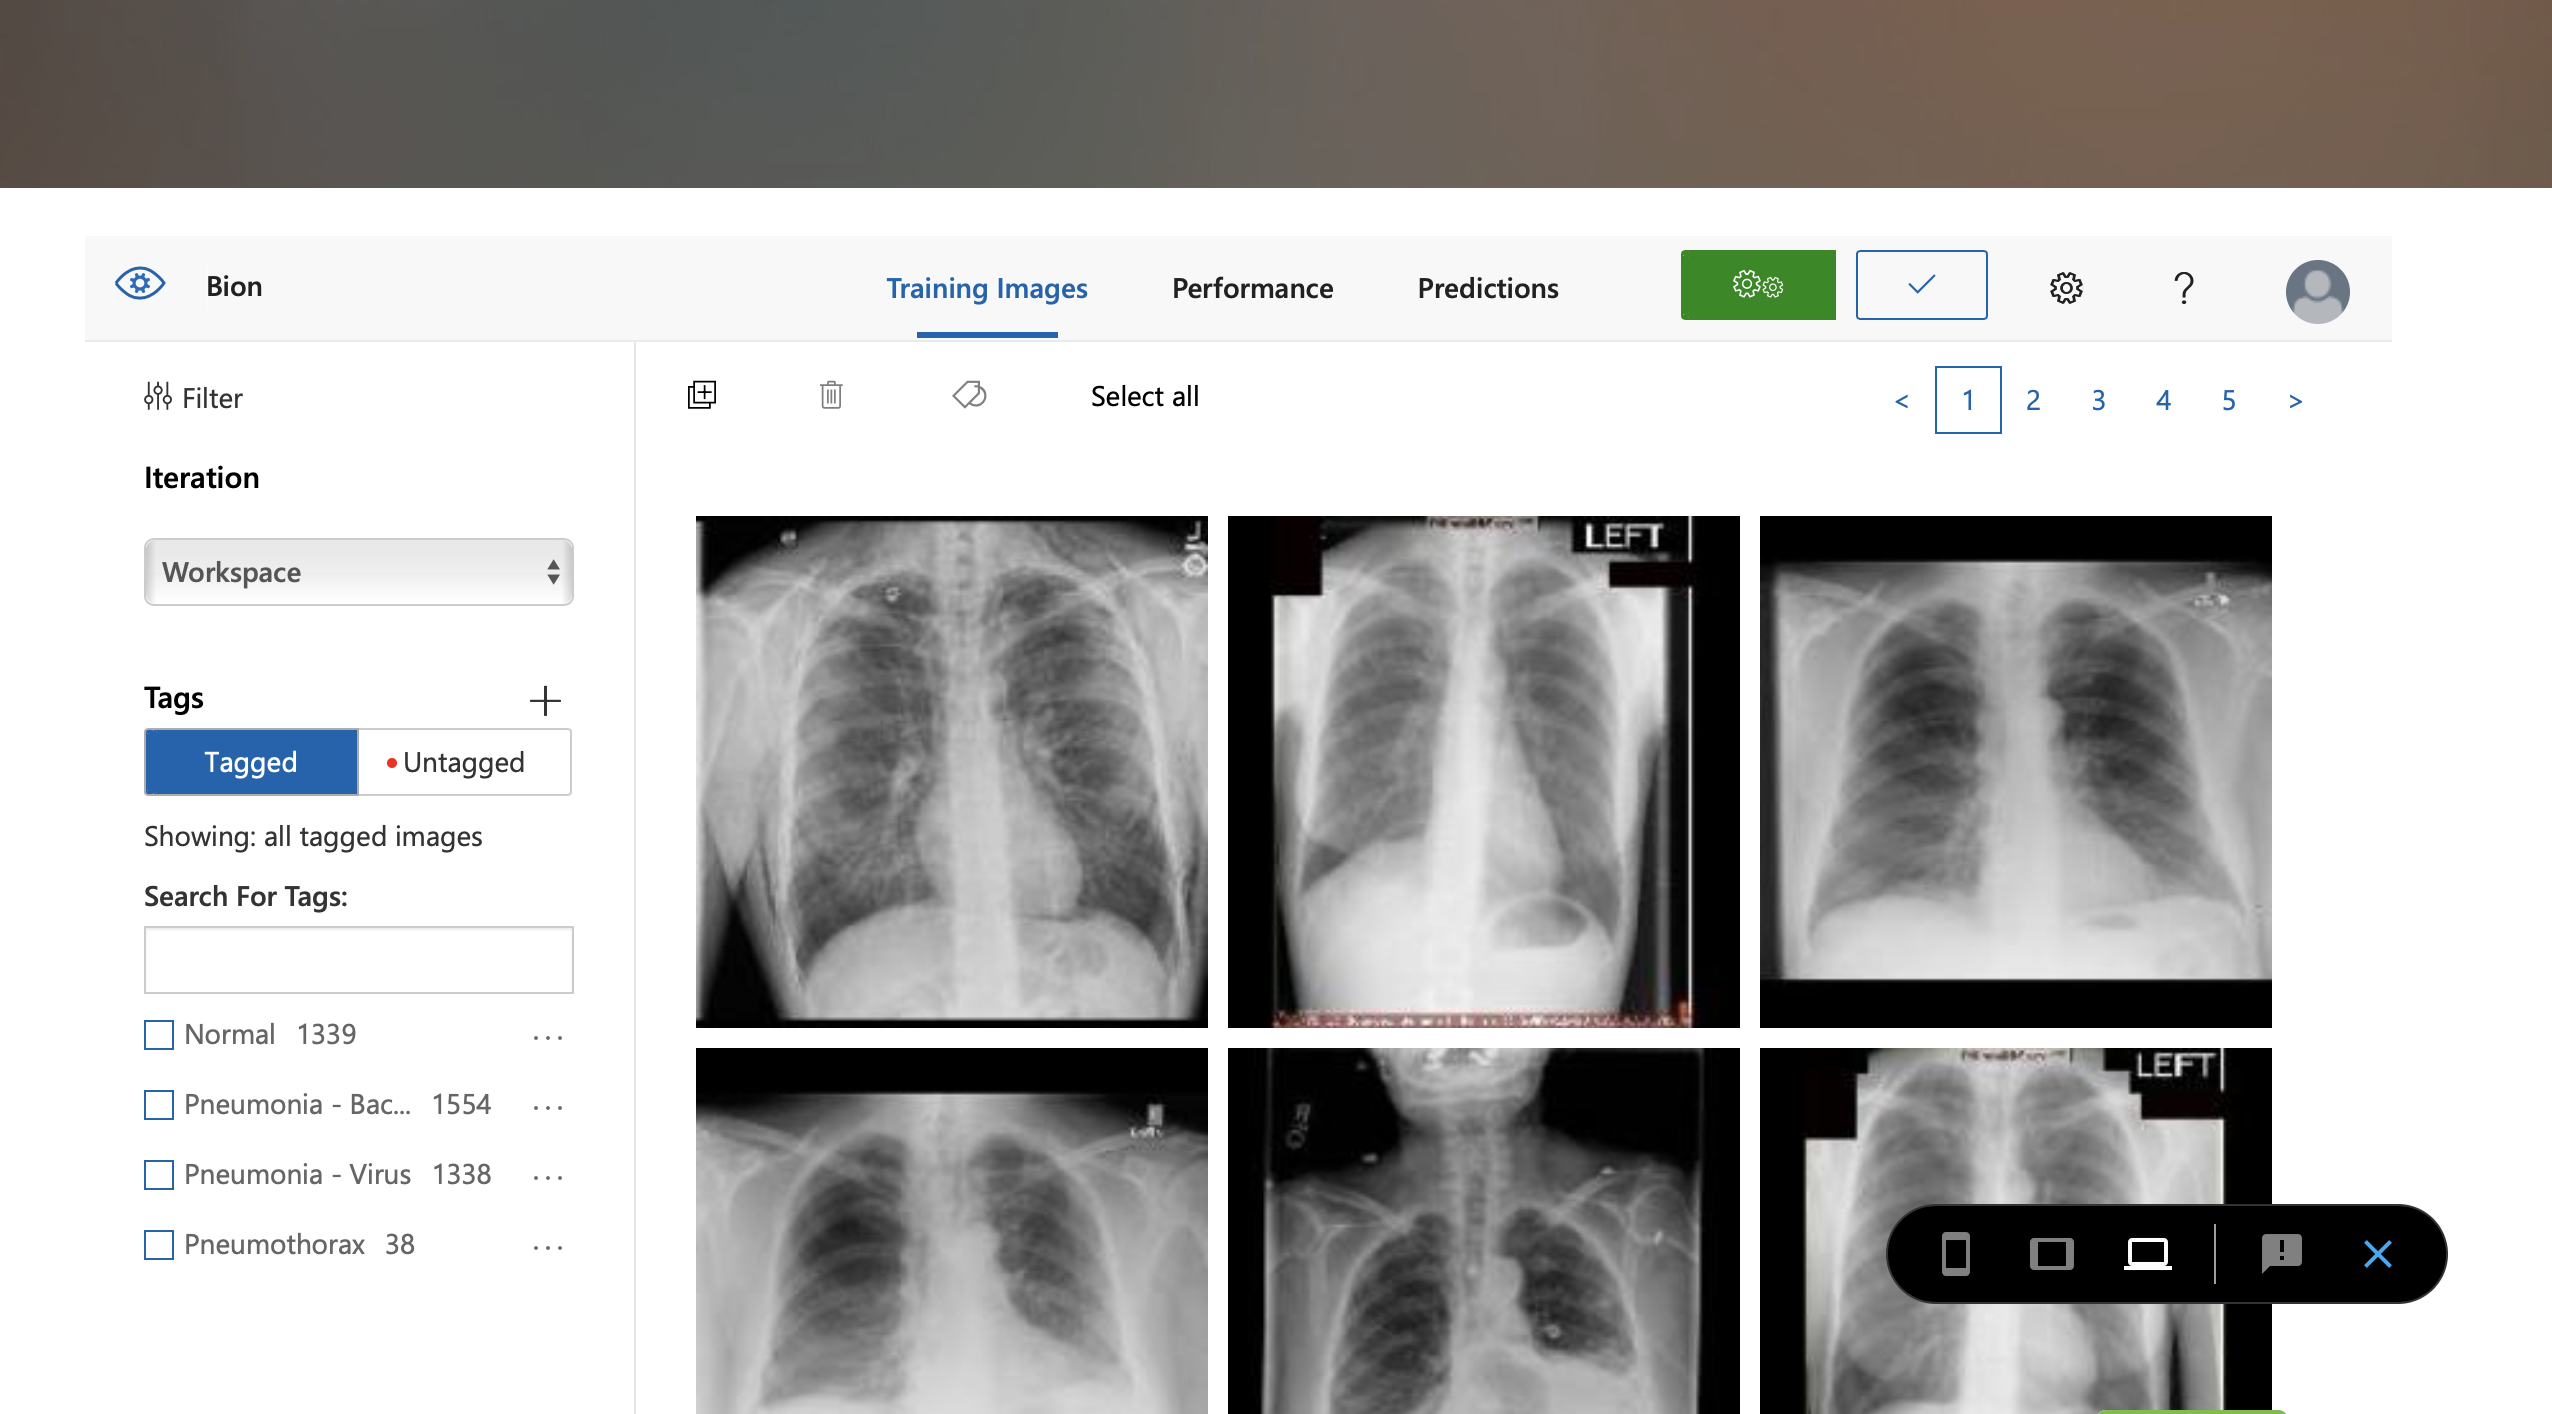

Bion is a Telemedicine Systems-Operation Platform for world-class physicians, high quality care, and user-friendly experiences which makes an Ideal Place for patients to get their primary care online. Bion uses Machine Learning Algorithms to diagnose different types of Pulmonary diseases through chest X-Rays.

We used Google's Inception v3, Azure's ML Platform, and Apple's CreateML.